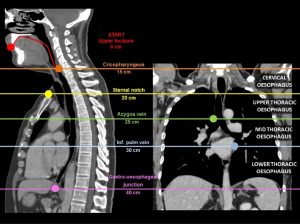

Physiologically, the UES consists of the cricopharyngeus muscle, the adjacent inferior pharyngeal constrictor, and the proximal portion of the cervical esophagus. UES innervation is derived from the vagus nerve, whereas the innervation to the musculature acting on the UES to facilitate its opening during swallowing comes from the fifth, seventh, and twelfth cranial nerves. The UES remains closed at rest owing to both its inherent elastic properties and neurogenically mediated contraction of the cricopharyngeus muscle.